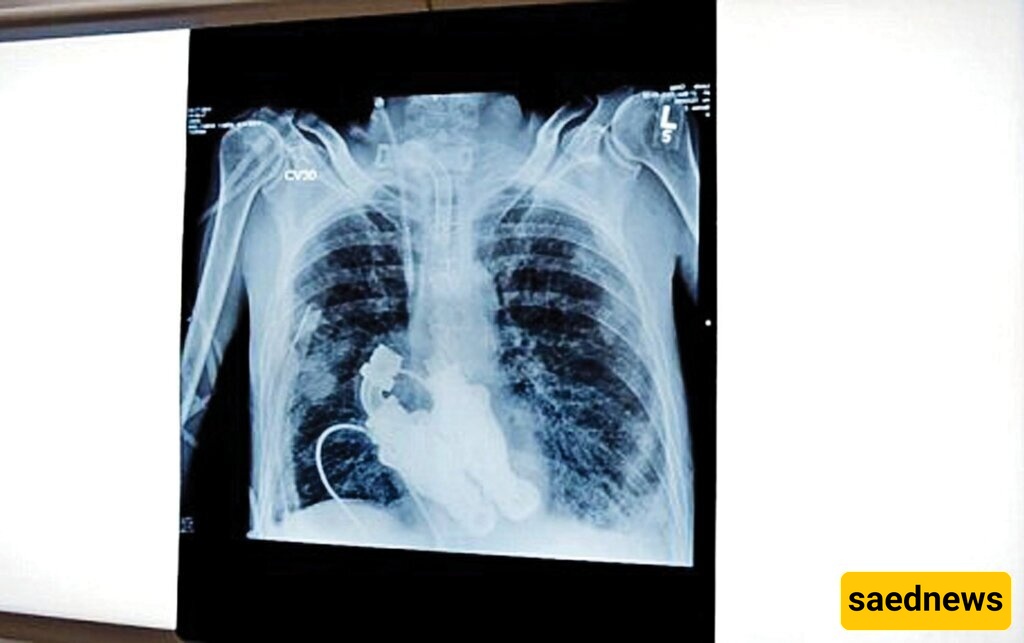

یعمل الجهاز المزروع فی صدر کریغ مثل التوربین، حیث یدفع الدم فی جسده. یستخدم مکونات عریضه تشبه الشفرات لتدویر الدم دون أی حرکه ضخ. وبینما یمتلک بعض المرضى، بما فی ذلک نائب الرئیس الأمریکی السابق دیک تشینی، أجهزه مشابهه، إلا أن تلک الأجهزه عادهً تساعد إحدى بطینَی القلب فقط، ولا تحل محل القلب بالکامل.

بقی کریغ فی وحده العنایه المرکزه. ووضع الأطباء والممرضون سماعات الطبیب على صدره، لکن لم یُسمع أی نبض—بل صوت خافت للدوامه فقط. وتذکرته زوجته لیندا بتفصیل: “استمعت بعنایه، وکل ما سمعته کان أزیزًا. کان أمرًا لا یصدق. لم یکن لدیه نبض—لأنه لم یکن لدیه قلب.”